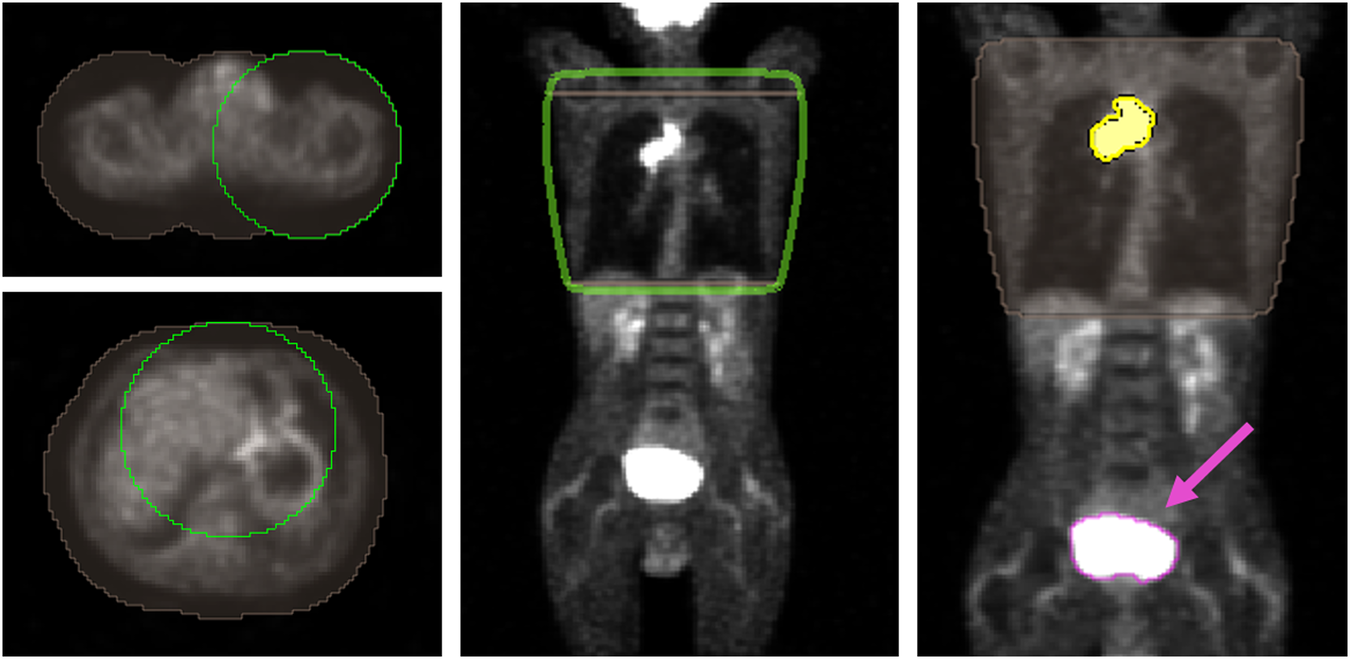

Finally, the model was tested with the 19 3D-PET images of patients prospectively recruited in 9 different centres involved in the PET-Plan trial. DSC(3D-PET) was 0.83 ± 0.11, improving 19% with respect to the accuracy for the COA-algorithm, with DSC(4D-COA) = 0.70 ± 0.12. It should be remarked that for patients who received whole-body PET scans, the AI-model also segmented the bladder and other tracer-enhanced pelvic structures. This limitation was avoided by a simple lung region restriction manually performed by interpolation of two regions of interest, Fig. 4. The time invested for this lung mask was comparable to the time required to place the seeds for the COA algorithm (< 1 min).

Fig. 4

Workflow for the lung mask creation: left regions of interest (brown) are manually delineated surrounding the body by a 50 voxel circle (green) in two slices located up and down the lung region; middle automatic interpolation is performed between the slices and lung region mask resulted (green) and (right) boolean intersection (yellow) between the AI segmentation and the lung region mask is obtained and consequently, the bladder region is rejected (segmentation pointed by the pink arrow)